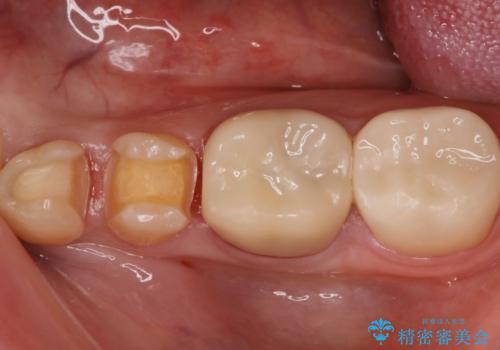

矯正終了し、かけたところをセラミックにて治したい。

- 矯正治療終了し、昔詰めていたセラミックが取れてしまったので再治療を希望っされた患者様です。

隣の歯も昔詰められていたものが劣化していたため日本治療させていただきました。

どちらも歯にピッタリとしていて、色も歯に調和していたため患者様に満足していただきました。